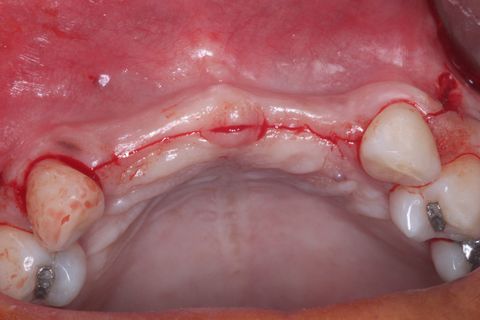

Novo procedimento cirúrgico após 6 mêses. Incisão

Descolamento Mucoperiosteal. Notar o ganho em expessura óssea.